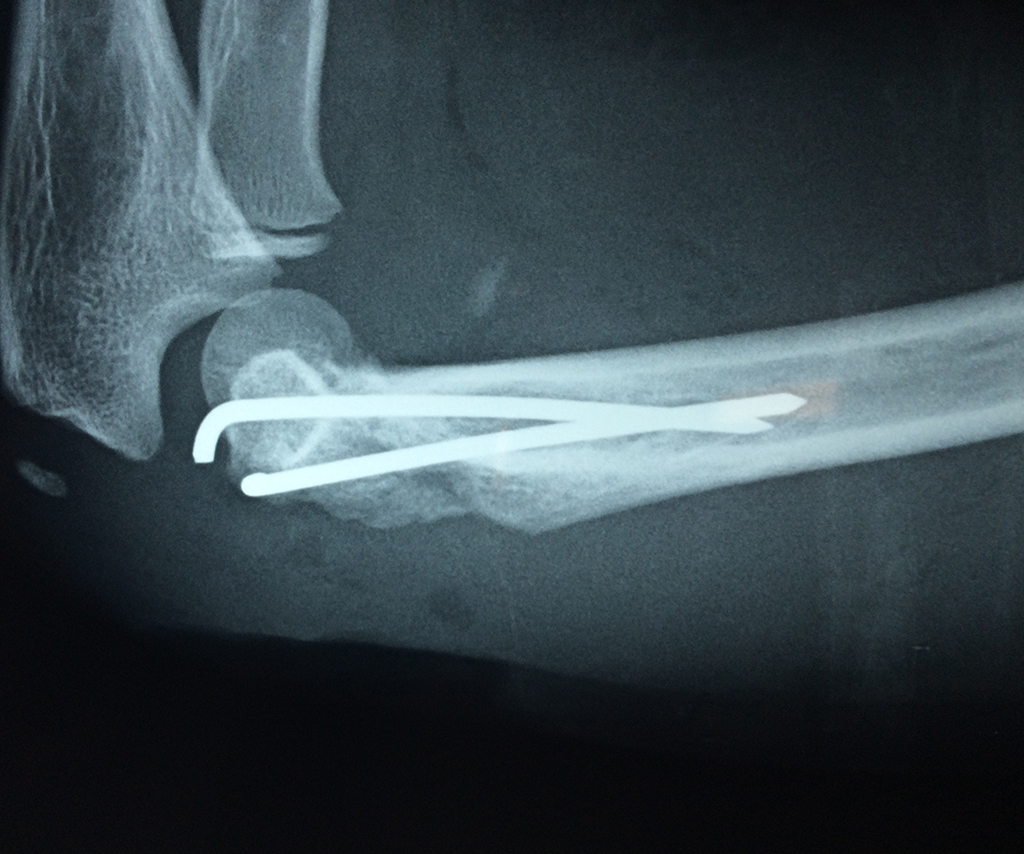

Cirugías de Hombros - Codo